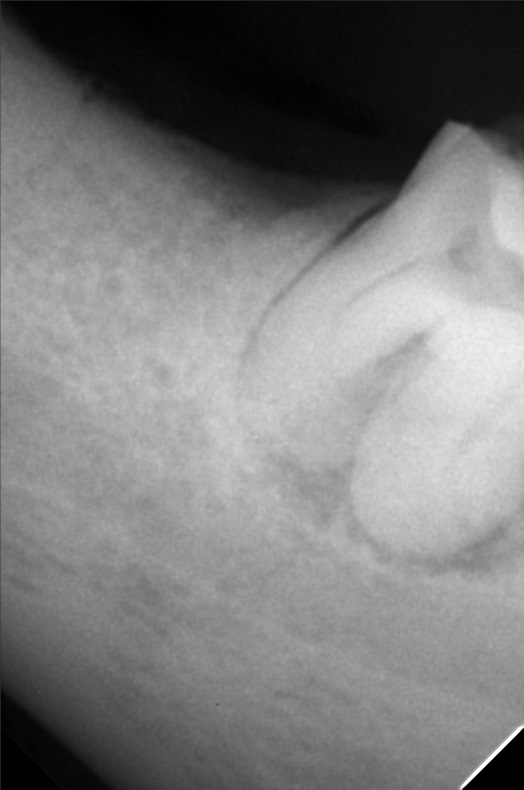

Edit Record Check our patient data records. Add patient information Patient Info Profile picture Last Name First Name Middle Name Birthdate Age Street Barangay City Country Zip Code Contact number Email Procedure 10-26-2019 > IRRIGATION / LASER > REMOVAL OF CROWN = 2,000 11-03-2019 > CROWN REMOVAL - 5 UNITS = 1,000 > 2 UNITS TEMPORARY =3,000 > UPPER DENTURE PARTIAL = 5,000 (IMMEDIATE DENTURE) 10/05/21- OP/ Lc 25/ Tf w/ eugenol 38 11/01/21- exo- 38/ exo Rf 16/ gingivectomy 34 resto gingival color 34/ laser hemostasis- 2 areas 11/12/21- suture removal 09/27/24 build up #24 LC #34 2 fiber post Alumina Crown-PHP 30,000 10/04/24 install of crown DP 15,000 Bal. 15,000 04/28/26 RCT | 20mm #32-camphenol #33-M,D,L Xray MTA 05/05/26 35mm file camphenol 05/13/26 RCT 2nd 3rd Incism & drainage laser hemostasis & antibacterial 6 celexocib File rodrigo_perez.jpg File 2 rodperez.jpg File 3 rod-urinalysis.jpg File 4 rod-hba1c.jpg File 5 rod-cbc.jpg File 6 rod-abg.jpg File 7 rod-ultrasound.jpg File 8 File 9 File 10 File 11 File 12 File 13 File 14 File 15 File 16 File 17 File 18 File 19 File 20 Retain Record Retain Record Yes No Save Your Changes